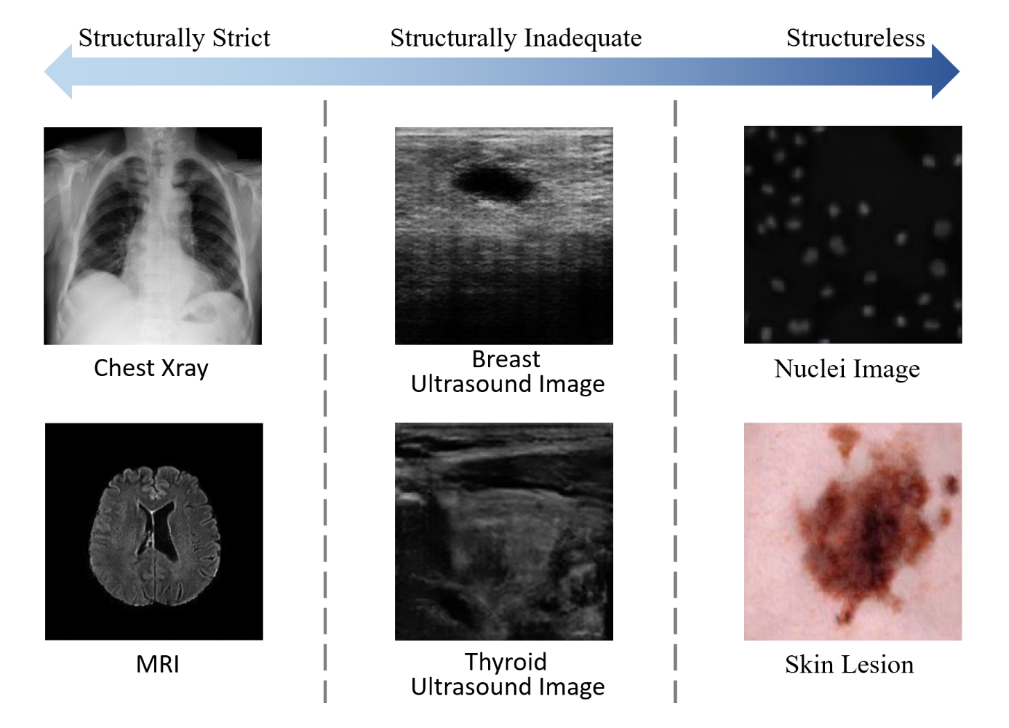

超声图像具有成像角度和尺度灵活多变的优势。但从另一角度来看,超声数据的结构不完善,导致生成的样本在超声图像中缺乏合法性。

图1中的甲状腺超声图像是我们先前研究的生成结果,其中气管和动脉的位置及特征完全偏离。

- 噪声向量:许多方法通过以一维噪声向量为输入,生成虚假的皮肤镜图像[10]、MRI图像[14]、胸部X光图像[15],以增强不平衡的图像数据集。对于较为复杂的数据如超声图像,Al-Dhabyani等人[8]关注于感兴趣区域(ROI),避免了结构不完整的乳腺超声图像所带来的问题。

大多数基于GAN的医学图像数据增强方法的数据具有一致或松散的结构。